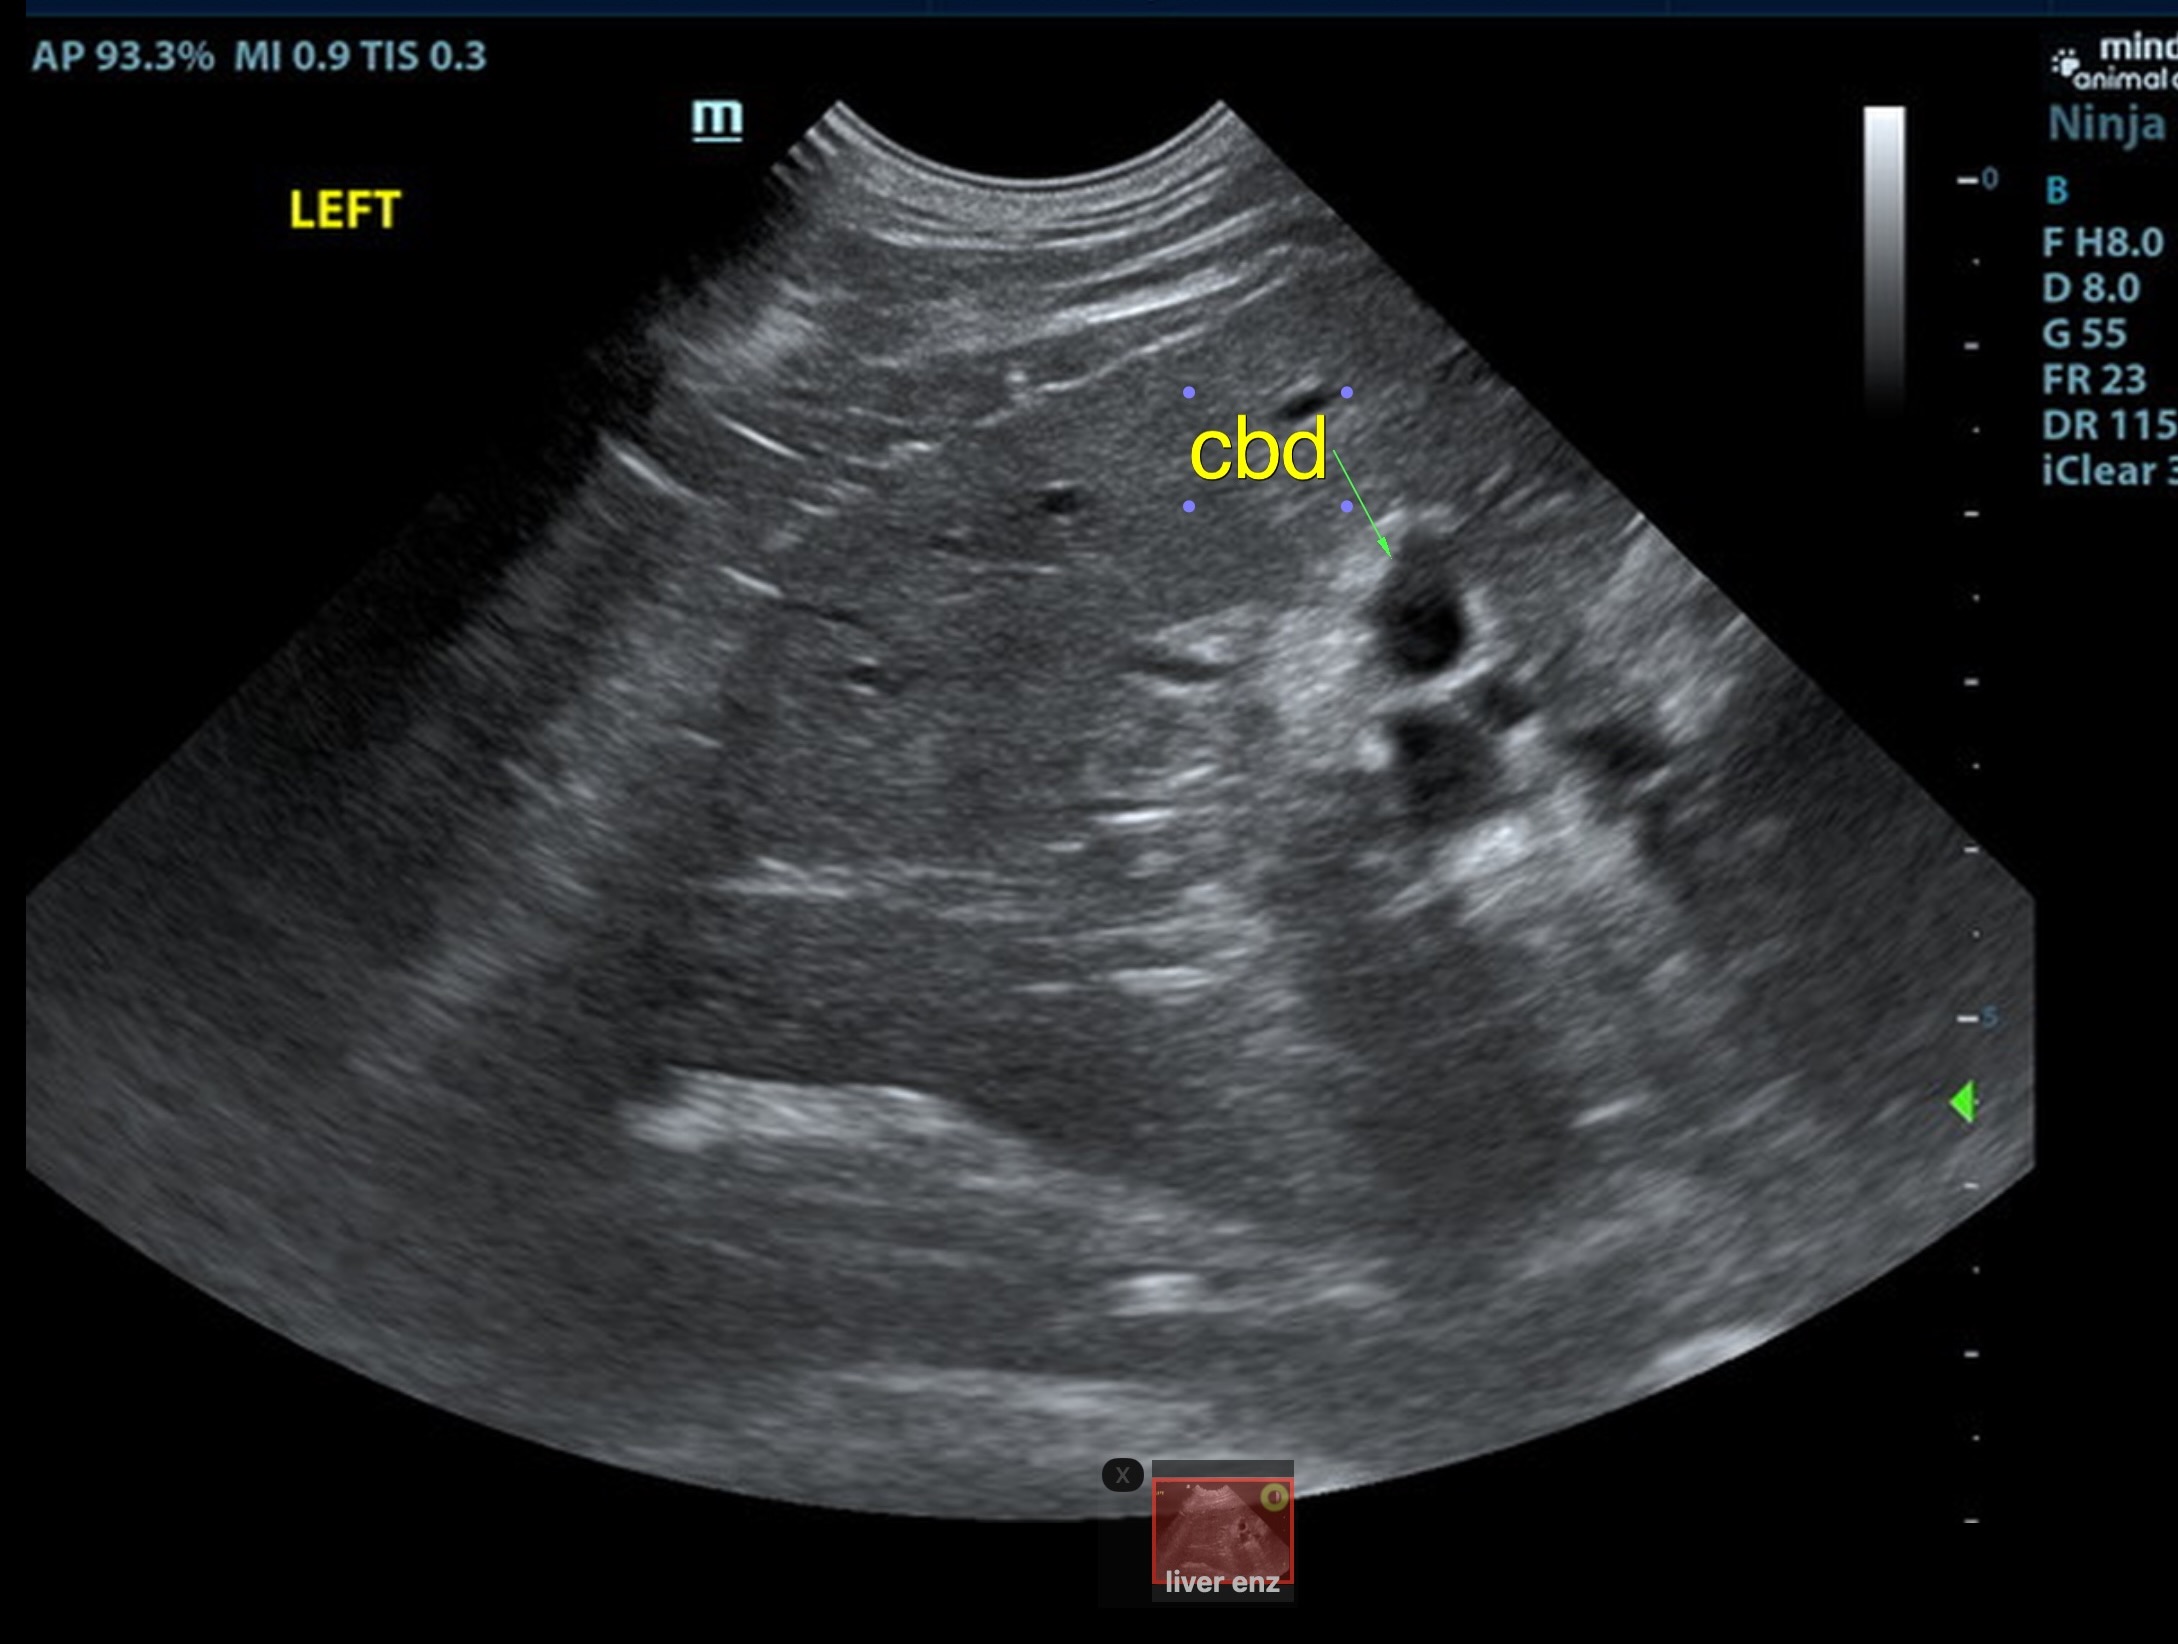

Local biliary duct dilation noted with post hepatic obstruction. Gallbladder was turgid. The common bile duct (CBD) was dilated with echogenic debris or possible tissue proliferation. The CBD measred 0.86 cm. An overt mass was noted at the common bile duct termination, measuring 2.0 cm. Target-type nodules noted in the liver.